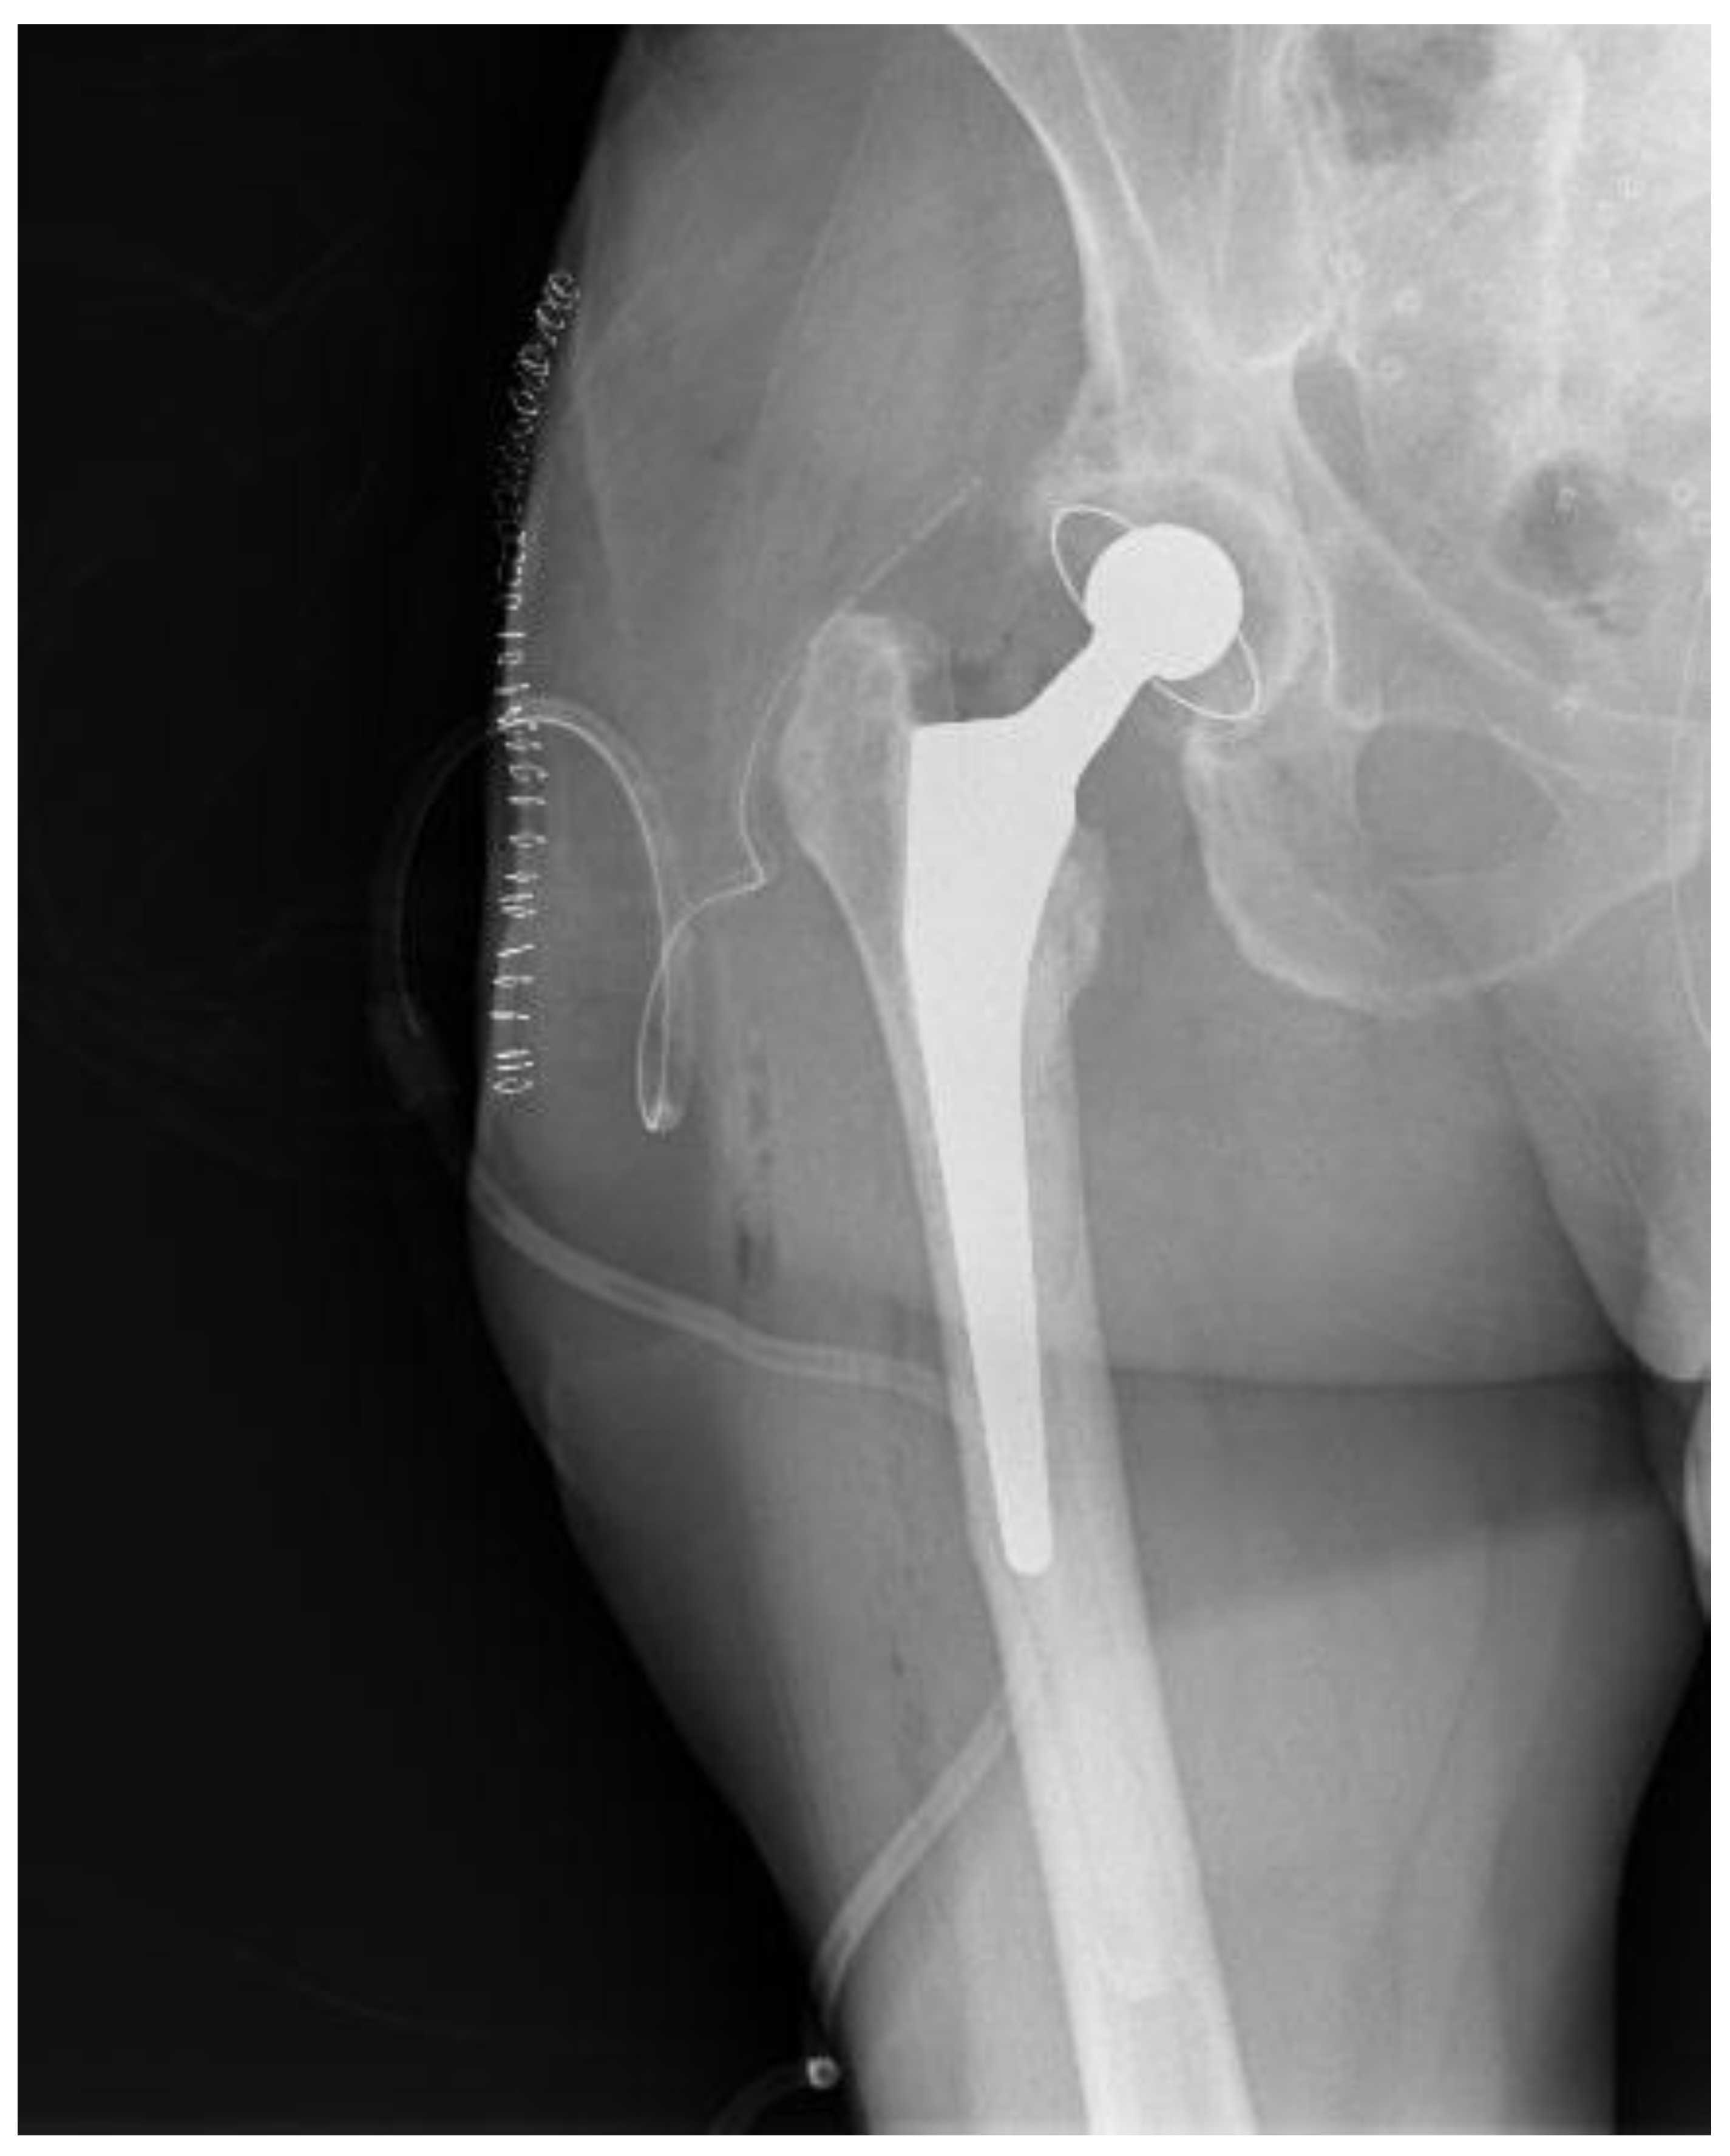

Taking into deliberation the presence of recurrent copious infections in our patient during the first postoperative year, the presence of an atypical pathogen responsible for the PJI and her entire past medical history, it was deduced that the patient might feature an impaired immune system. Consequently, the risk of revision THA surgery was regarded as highly elevated. She was referred to a preeminent immune system specialist physician. Still, no solid inferences could be drawn to explain the multiple infection incidents, albeit without excluding the notion of a weakened immune system. The patient continued to complain about considerable hip pain and an inability to sustain full weight bearing since she had the hip spacer for an extended period and insisted on having a new hip operation. She was thoroughly counselled that, if a revision THA was performed, the peril of a potential new PJI was exceptionally high. Eighteen months from the spacer placement, the patient featured no clinical infections or hospitalizations during the last 5.5 months with negative inflammatory markers and no indications of hip wound infection. After diligent consent, the patient was reoperated on, and a typical revision THA (Avenir Femoral Stem and ZCA All-Poly Acetabular Cup, Zimmer Biomet Holdings Inc., Warsaw, Indiana, United States) was executed utilizing the same posterior approach that was employed in the first operation at our Institution (Figure 4). Intraoperatively, no evident indications of remaining infection were observed regarding the bones and surrounding soft tissues, while bone stock was sufficient. In case that any tissue or fluid with the suspicion of infection was presented in the operating field, no new arthroplasty materials would have been implanted.

Figure 4. Postoperative hip X-ray after revision THA.